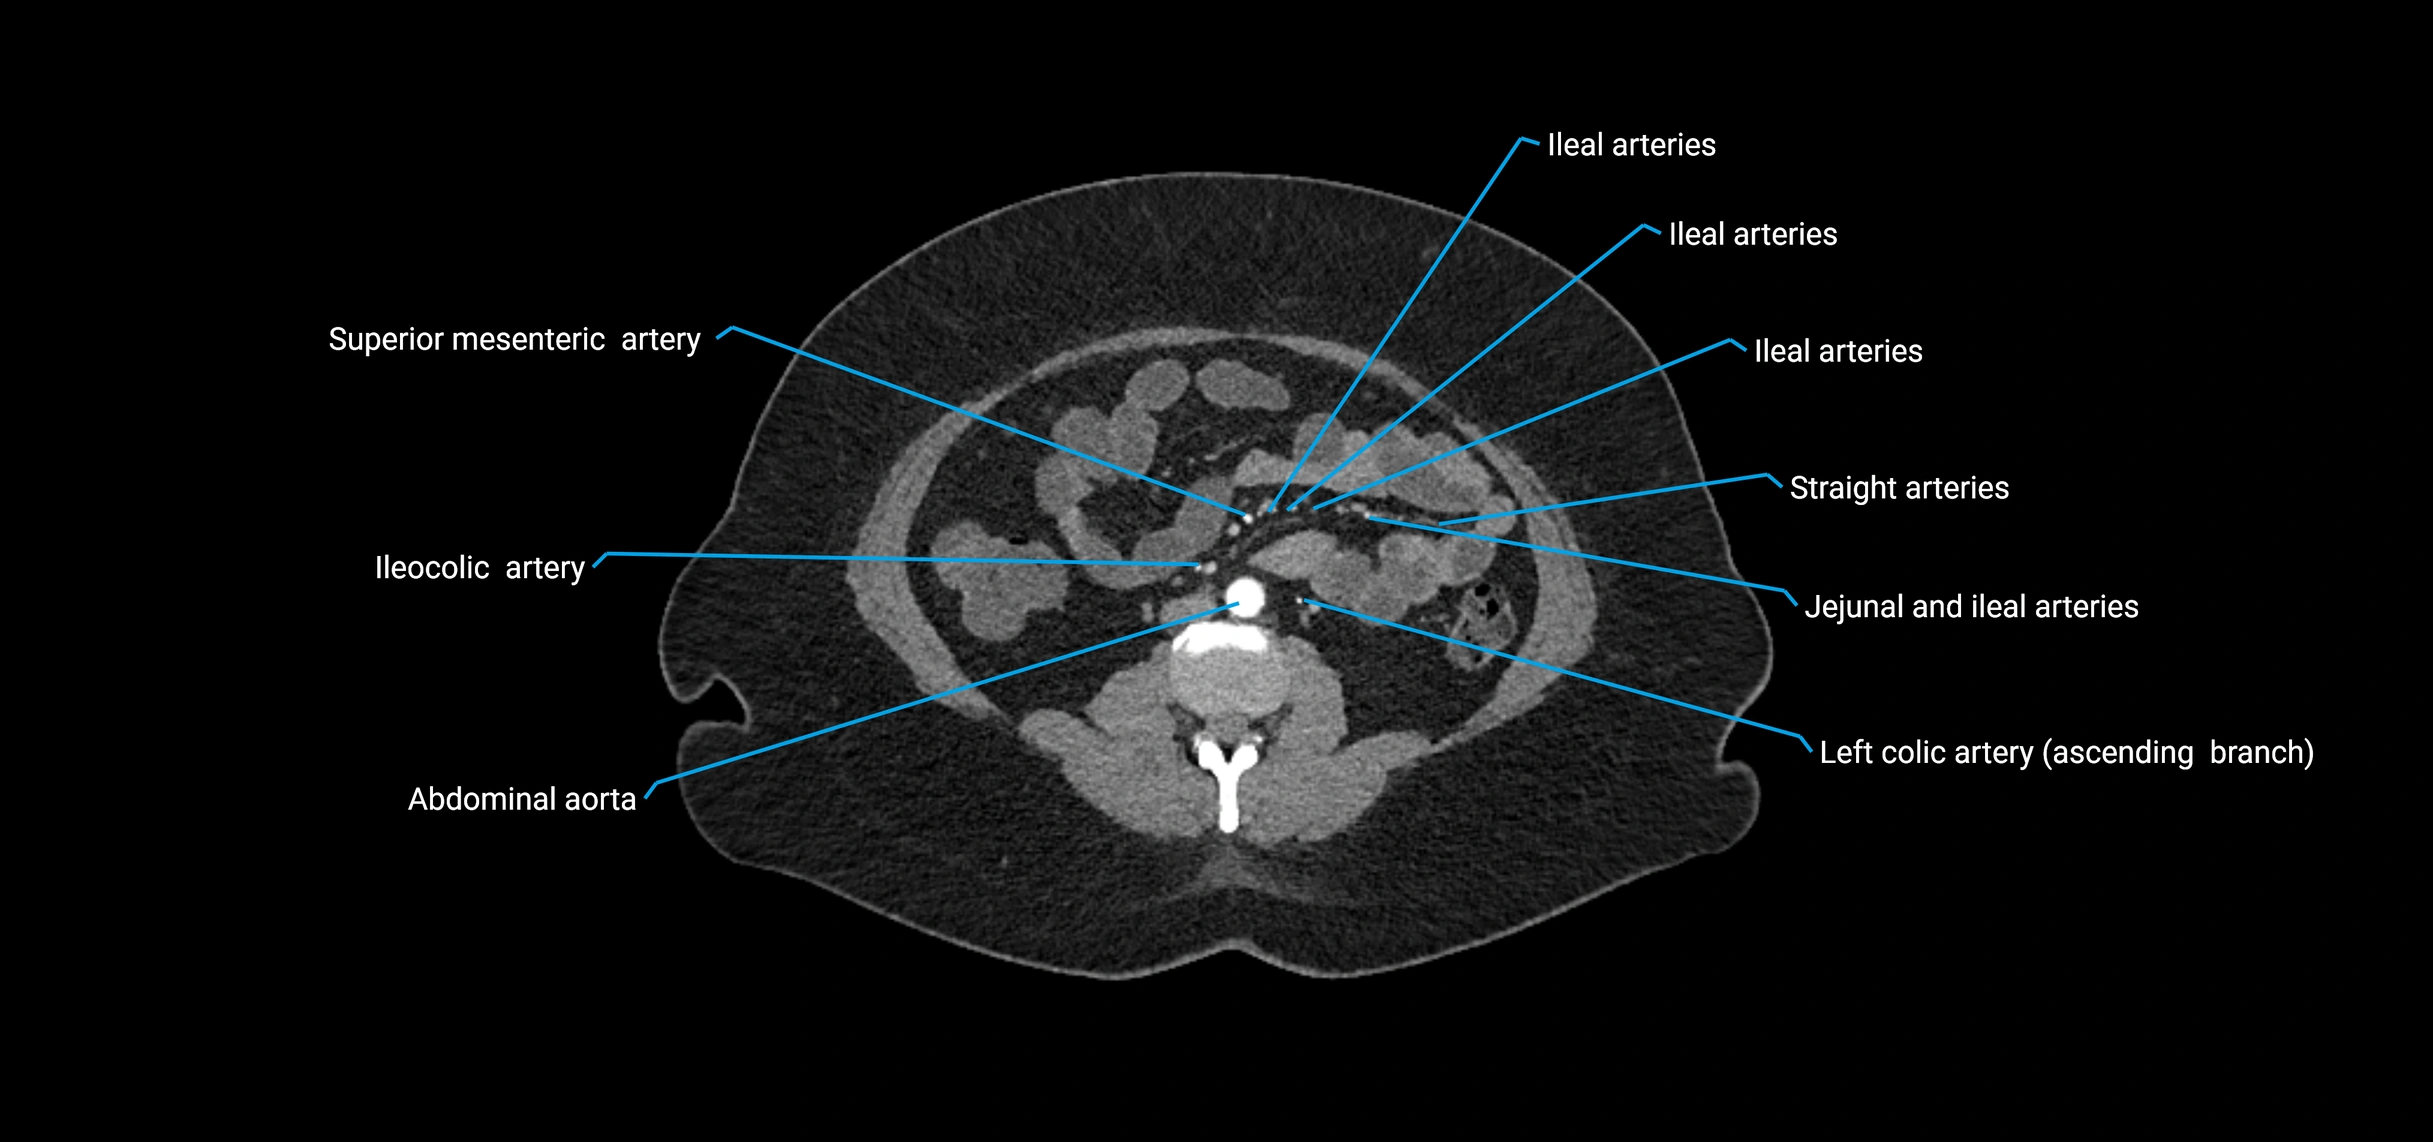

Contrast-enhanced CT (CTA):

• Gold standard for abdominal aortic imaging

• Provides excellent detail of lumen, wall, aneurysm, thrombus, and branch vessels

• Multiplanar and 3D reconstructions help in aneurysm measurement, stent graft planning, and dissection evaluation